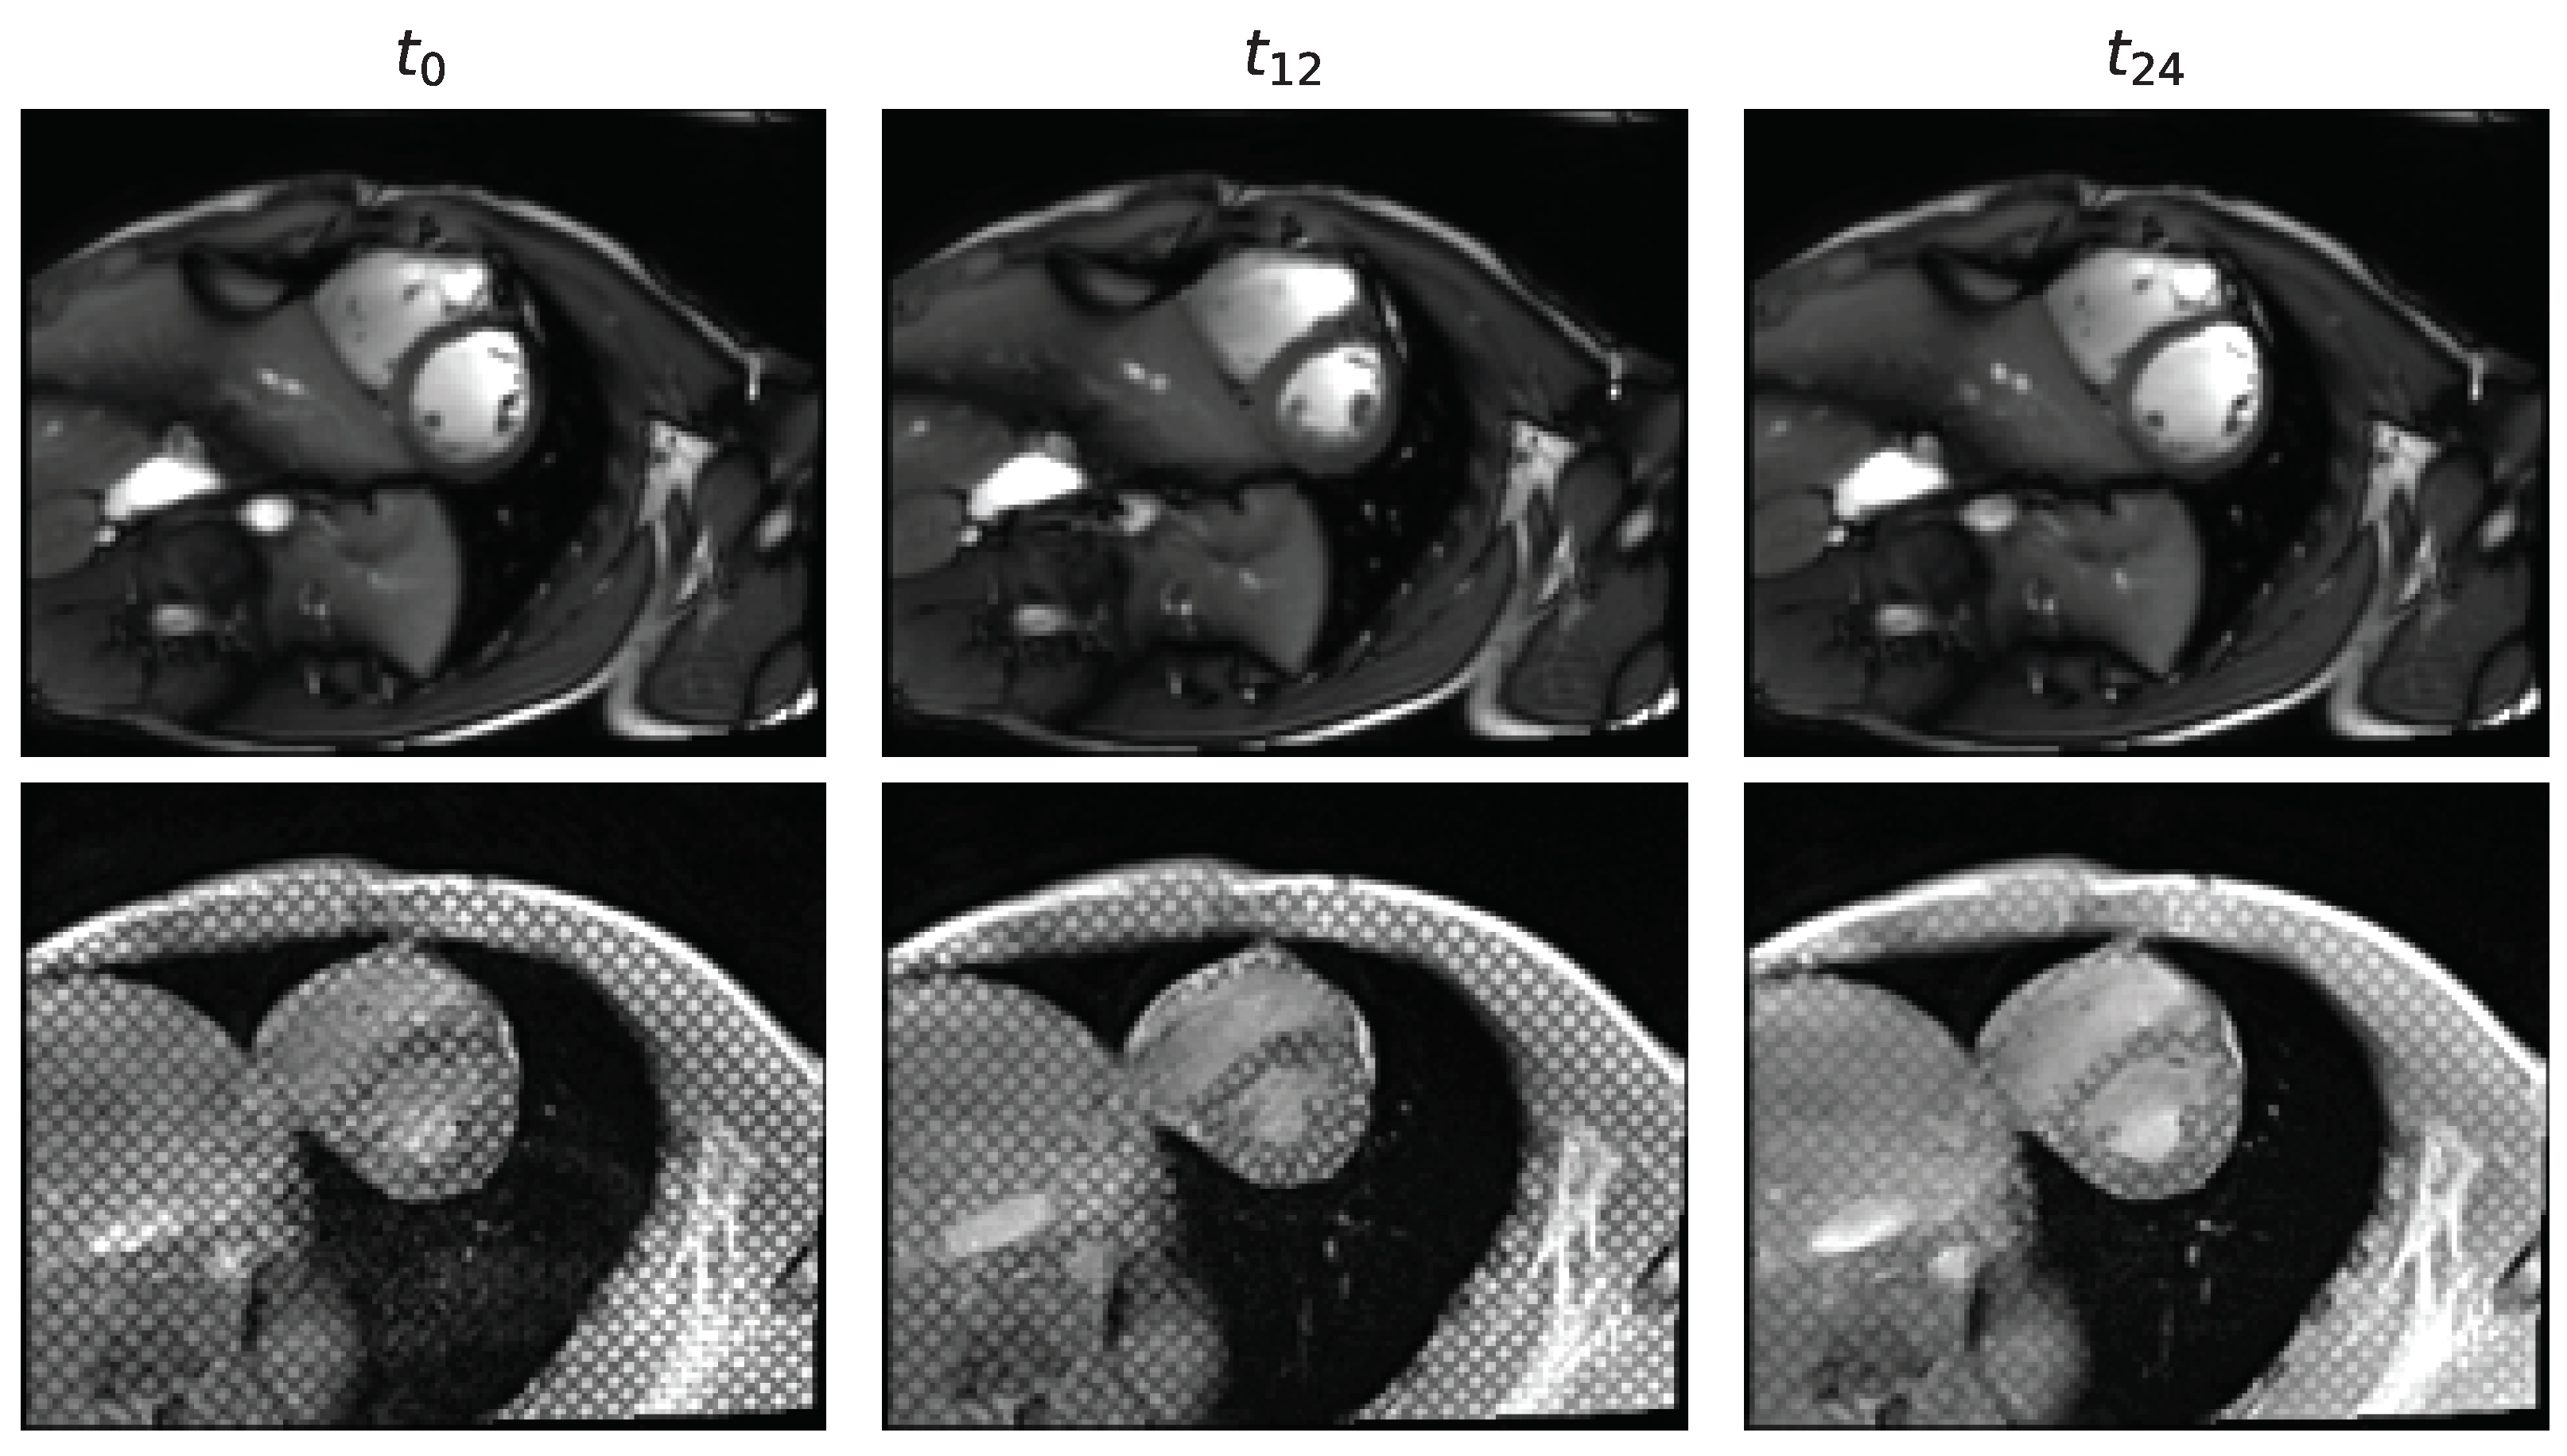

3.1. Unpaired and Unlabeled Cine to Tagged Image Transformation

3.2. Segmentation of the Myocardium in Tagged CMR Images

4.1. Analysis of the Cine to Tagged Image Transformation Models